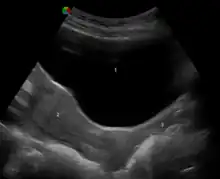

Under the influence of maternal estrogen, the vagina of a newborn is lined by thick stratified squamous epithelium (or mucosa) for two to four weeks after birth. Between then to puberty, the epithelium remains thin with only a few layers of cuboidal cells without glycogen.[39][42] The epithelium also has few rugae and is red in color before puberty.[4] When puberty begins, the mucosa thickens and again becomes stratified squamous epithelium with glycogen containing cells, under the influence of the girl's rising estrogen levels.[39] Finally, the epithelium thins out from menopause onward and eventually ceases to contain glycogen, because of the lack of estrogen.[10][38][43]